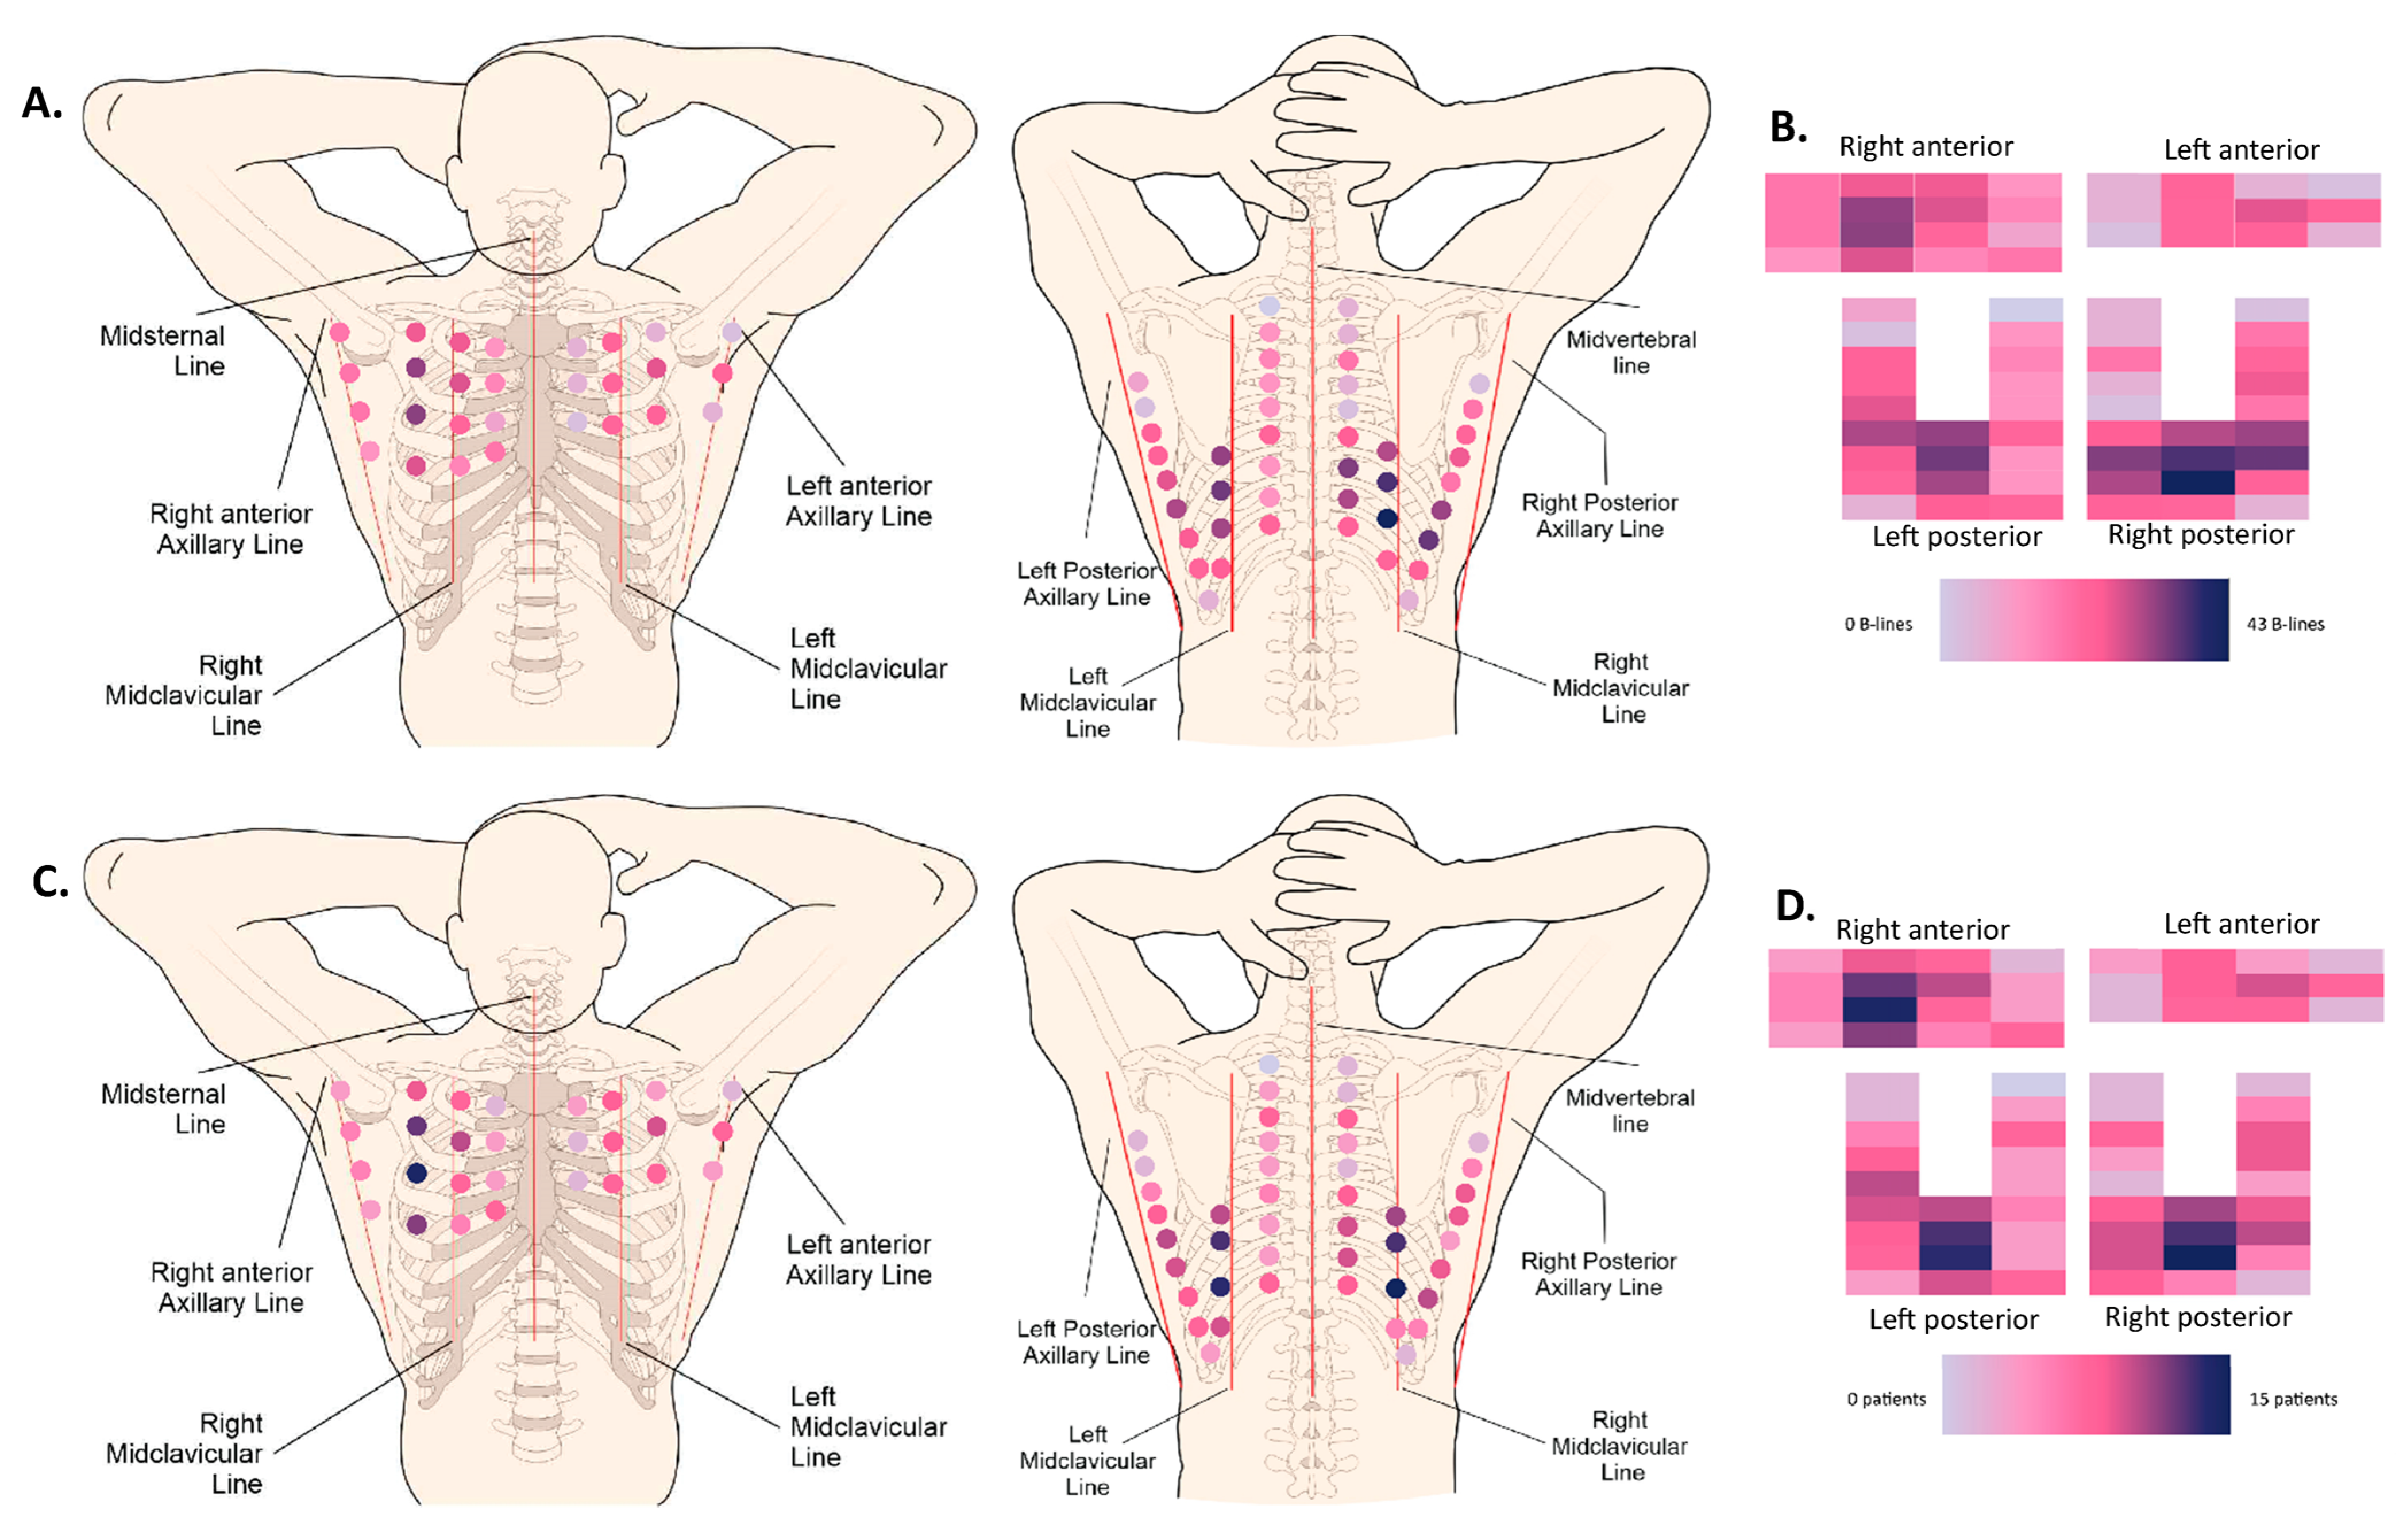

3. Results

3.2. LUS Patterns

4. Discussion